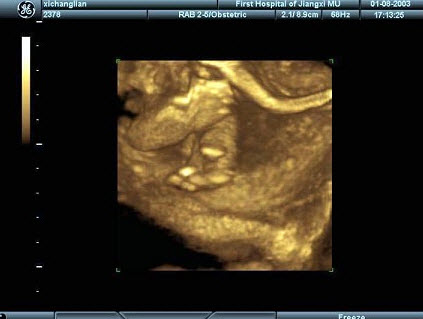

51、单项选择题

女性,25岁,停经35周。产前超声检查,图像显示的是胎儿的()

A.脊柱

B.肢体

C.颜面部

D.胸腔

E.胎头